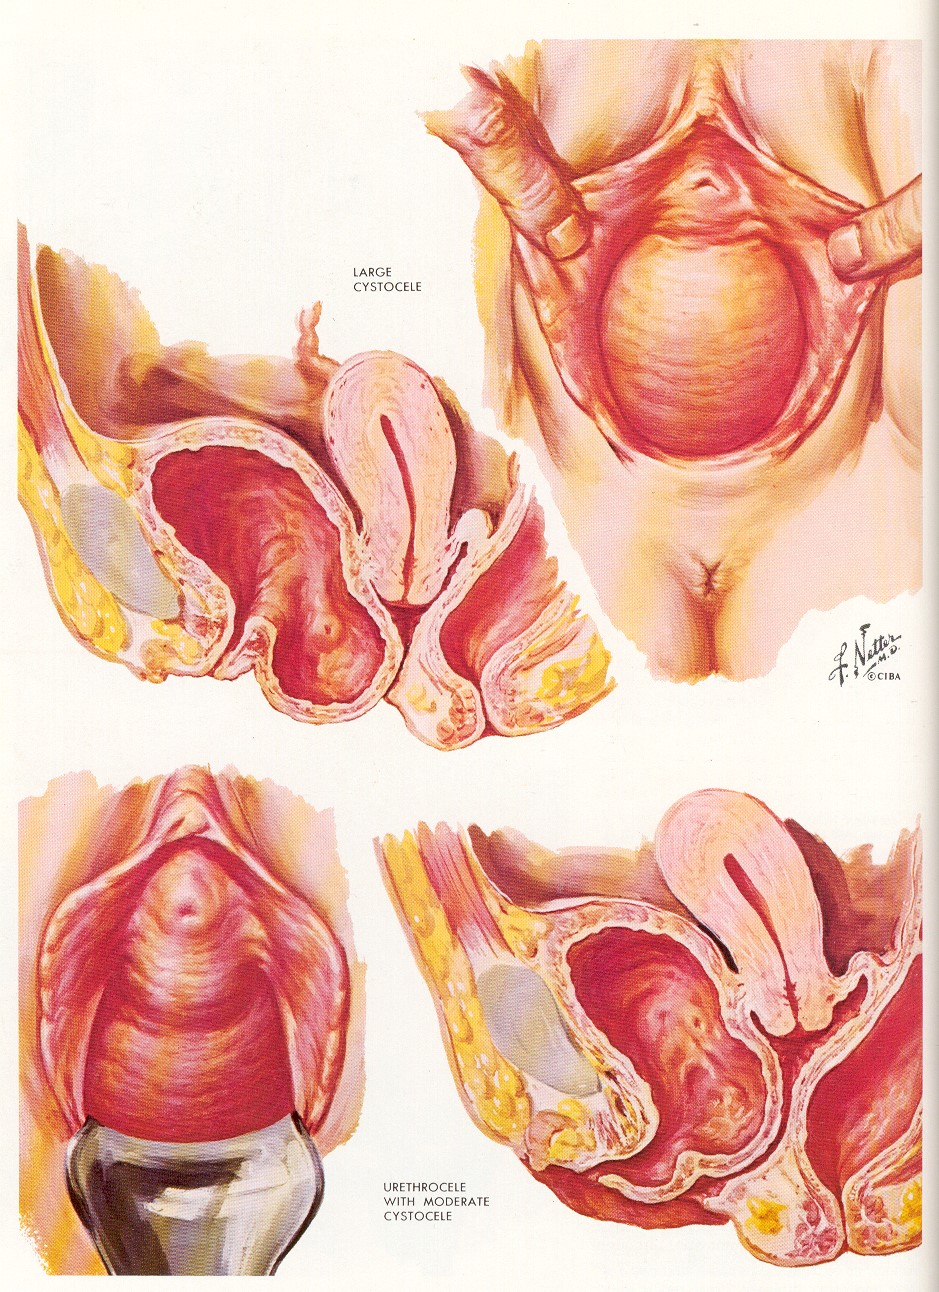

Чаще всего опущение или выпадение стенок влагалища происходит вследствие тяжелых естественных родов или родов крупным плодом. Опущение передней стенки влагалища сопровождается перемещением мочеиспускательного канала и мочевого пузыря, что может привести к частым циститам, стрессовому недержанию мочи, частым мочеиспусканиям. При опущении передней стенки влагалища у женщин обостряются хронические вагиниты, поскольку происходит постоянное нарушение флоры. Консервативное лечение воспаления слизистой влагалища в таком случае, как правило, не приводит к успеху, так как необходимо устранить причину заболевания и применить хирургический метод лечения.

При опущении передней стенки влагалища у женщин обостряются хронические вагиниты, поскольку происходит постоянное нарушение флоры. Консервативное лечение воспаления слизистой влагалища в таком случае, как правило, не приводит к успеху, так как необходимо устранить причину заболевания и применить хирургический метод лечения.

Пластика передней и задней стенок влагалища с одномоментной установка сетчатого импланта (слинг-системы) позволяет избавиться от перечисленных тревожных симптомов, восстановить положение матки, уретры, мочевого пузыря и укрепить мышцы тазового дна. Имплант обладает 100% биосовместимостью с тканями человеческого организма.

Вагинопластика предназначена для хирургического сужения влагалищного канала и включает удаление избыточной слизистой оболочки влагалища из сводов влагалища.Он может включать переднюю кольпорафию, заднюю кольпорафию, иссечение латеральной слизистой оболочки влагалища или различные комбинации этих хирургических методов (рис.). Некоторые хирурги также проводят пластику леватора по средней линии, чего, по нашему мнению, лучше всего избегать, так как это может вызвать выраженную диспареунию.

Вагинопластика предназначена для хирургического сужения влагалищного канала и включает удаление избыточной слизистой оболочки влагалища из сводов влагалища.Он может включать переднюю кольпорафию, заднюю кольпорафию, иссечение латеральной слизистой оболочки влагалища или различные комбинации этих хирургических методов (рис.). Некоторые хирурги также проводят пластику леватора по средней линии, чего, по нашему мнению, лучше всего избегать, так как это может вызвать выраженную диспареунию.